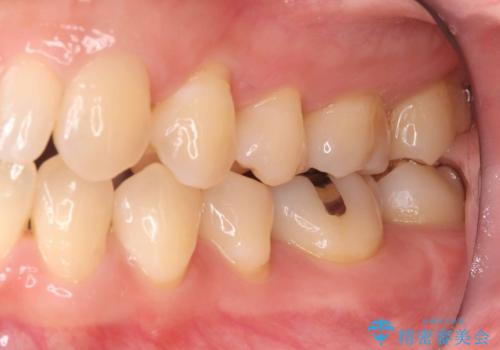

歯が欠けたことによるものか、もしくは以前装着された修復物の不適合が原因と考えられますが、銀歯(メタルインレー)と歯との間に大きな段差が認められ、汚れが溜まりやすい状態となっていました。

今回は、経年的な劣化が少なく、汚れが付着しにくいセラミックインレーを用いて治療を行いました。